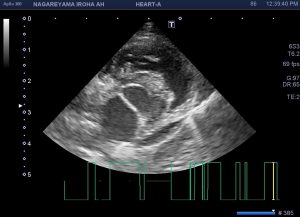

レントゲン検査の説明をする先生

実は、説明中に写真を撮ろうとしたら

わざわざそれらしいポーズを取ってくださいました

(おちゃめさん♡)